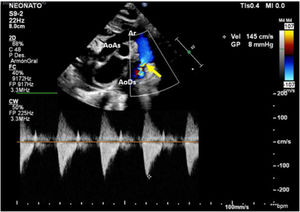

Caso clínicoPaciente masculino con diagnóstico prenatal de CoA, nacido a término por vía vaginal con Apgar 9/9. Se realiza una ecocardiografía al nacimiento en la que se confirma el diagnóstico de CoA no dependiente de ductus, con un gradiente a nivel del istmo de 8mmHg, con buena función biventricular y ductus arterioso cerrado (fig. 1). Recibe prostaglandinas por vía intravenosa durante 12 h (bolo inicial de 0,1 μg/kg/min y dosis posterior 0,03 μg/kg/min), suspendiéndose tras comprobarse la no apertura del ductus y la estabilidad del paciente.